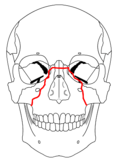

| Le Fort II fractures | |

At the beginning of the 20th century, René Le Fort mapped typical locations for facial fractures; these are now known as Le Fort I, II, and III fractures (right).[6] Le Fort I fractures, also called Guérin or horizontal maxillary fractures,[13] involve the maxilla, separating it from the palate.[14] Le Fort II fractures, also called pyramidal fractures of the maxilla,[15] cross the nasal bones and the orbital rim.[14] Le Fort III fractures, also called craniofacial disjunction and transverse facial fractures,[16] cross the front of the maxilla and involve the lacrimal bone, the lamina papyracea, and the orbital floor, and often involve the ethmoid bone.[14] are the most serious.[17] Le Fort fractures, which account for 10–20% of facial fractures, are often associated with other serious injuries.[14] Le Fort made his classifications based on work with cadaver skulls, and the classification system has been criticized as imprecise and simplistic since most midface fractures involve a combination of Le Fort fractures.[14] Although most facial fractures do not follow the patterns described by Le Fort precisely, the system is still used to categorize injuries.[5]